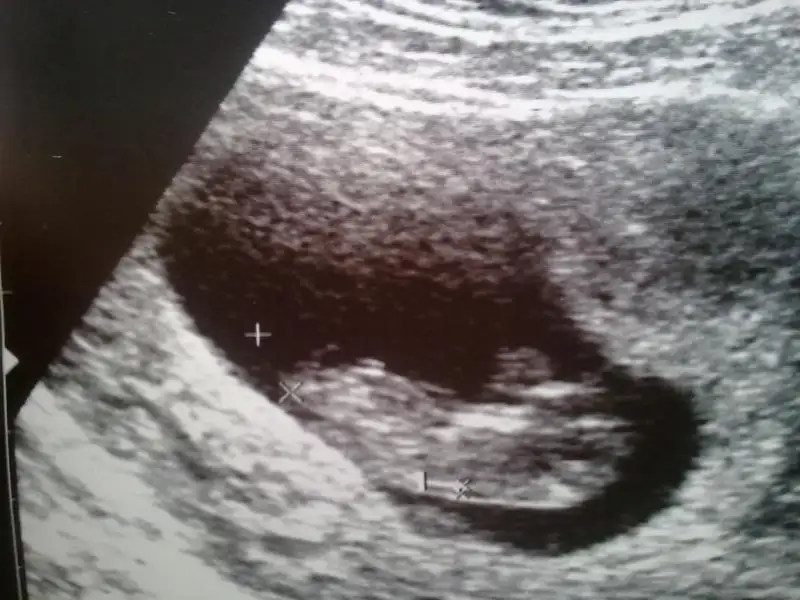

dr soylemeden siz gorun genital nub teorisi ( bebegin cinsiyeti)

yine de bir tahmin alayım orkdm çok olmuyorsam nub tam paralel degil sanki 30 luk açı var gibi bana göre ama testis falan da göremedim ben yine de bir bakarmısın buna? sf175

eger o kiyidaki nub ise ki pozisyon hic uygun degil kiz olabilir